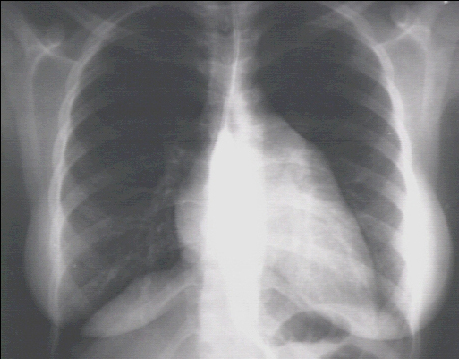

These chest X rays show left ventricular enlargement and left atrial enlargement. This PA view demonstrates the enlarged left ventricle as an increase in the inferolateral cardiac border associated with an increased cardiothoracic ratio. The markedly enlarged left atrium is manifested by the double contour within the heart border, an elevated left mainstem bronchus, and an enlarged left atrial appendage.

The lateral view with barium swallow, demonstrates posterior displacement of the esophagus by the markedly enlarged left atrium.